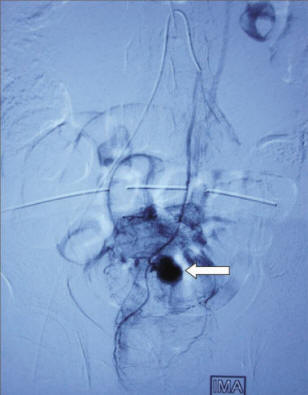

embolization Of A Gi Bleed - Endovascular Today

Embolization of a Gi Bleed (approximately 2:00 AM) with rectal bleeding. When she arrived to the hospital, she was hemody-namically stable but had further rectal bleeding. After Embolization is a quick and effective treatment for lower GI bleeding.n ... Read Here